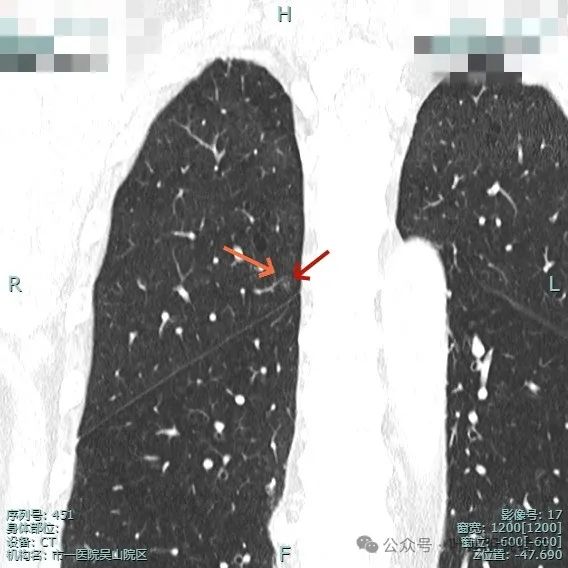

再看靶重建的影像:

右上结节虽小,但轮廓较清,邻近有小血管走行,两者之间有缝隙,说明不太像肺内淋巴结或普通急性炎症。

其实密度不太纯,边缘显毛糙,离叶间裂近,但叶间裂无明显牵拉。

中间似有血管穿行,离胸膜也近的,整体轮廓较清。

此灶考虑肿瘤范畴的可能性大,微浸润性腺癌或不典型增生可能性大,有时细支气管腺瘤也会类似表现。总体可先随访,反正它也不是主病灶。